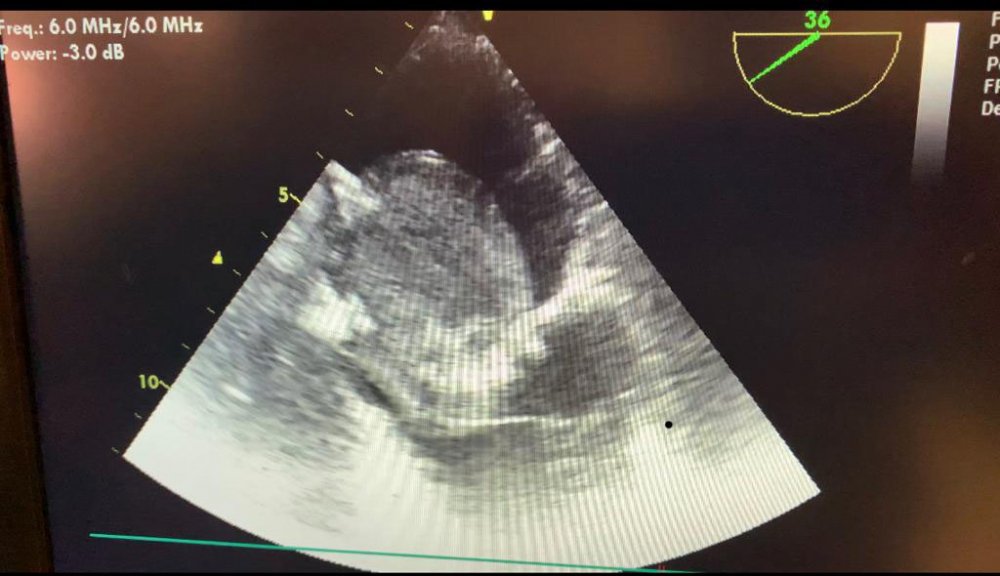

MCBÜ Tıp Fakültesi Kalp ve Damar Cerrahisi Anabilim Dalı Öğretim Üyesi Prof. Dr. Ömer Tetik, kalp tümörlerinin çok fazla bilinmediğini, ancak ani ölümlere neden olabildiğini söyledi. Nurettin Nurioğlu’nun kalbinden başarılı bir ameliyatla çok büyük bir tümör çıkardıklarını kaydeden Prof. Dr. Tetik, “ Hastamızda 7 santimetrelik bir tümör mevcuttu ve gerçekten büyüktü. Kalbin her kasılmasında kapakçığın içine giriyor ve kalbin içine kan akışını engelliyordu. Buna bağlı olarak vücuda kan gelmiyor. Hastada ciddi nefes darlığı vardı. Kalbin kan akışı engelleniyordu. Bu hastalarda da genellikle ani ölümler olabiliyor. Hastamızın otobüs şoförü olduğu düşünüldüğünde de çok tehlikeli bir durum yaşanabilirdi. Yaptığımız testler sonucu tümörü saptadık ve en kısa zamanda açık kalp ameliyatı ile tümörü çıkardık” dedi.

Kalp tümörlerinde tanı koymanın çok önemli olduğunu belirten Prof. Dr. Tetik, nefes darlığı olan kişilerin mutlaka kardiyologa yönlendirilmesi gerektiğini söyledi. Prof. Dr. Tetik, “Kalp tümörleri iyi huylu ve kötü huylu olmak üzere ikiye ayrılıyor. Kalp tümörlerinin yüzde 75’i iyi huylu. Özellikle erişkinlerde miksoma isimli kalp tümörleri kalbin sol kulakçıkta yerleşir. Kalp tümörleri yerleşim yerlerine göre tehlikelidir. Ani ölümlere neden olabilirler” diye konuştu.